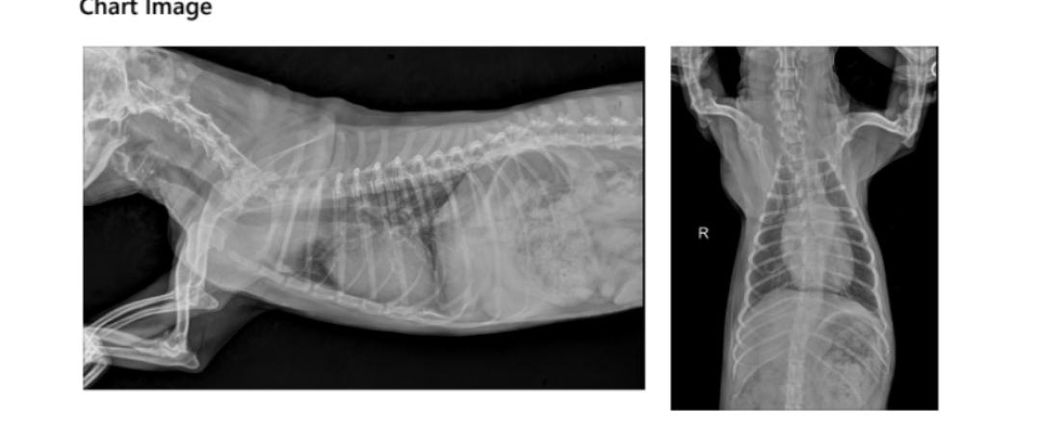

엑스레이에서는 안보이는 이유와

이게 갑자기 생길수도 있는건지 오래된건지도 궁금해요..(지금까지 엑스레이 찍어오면서 들은적이 없어요)

매우 작은 공기주머니로 구성되어 있는 폐실질 내부에 공기가 차있는 bulla가 들어 있으면 엑스레이상에서는 상당히 커기지 전까지 관찰되지 않는게 정상입니다. 즉, CT검사의 민감도가 높아서 잘 보이는것일 뿐 방사선에서 보이지 않는건 일반적인 현상입니다.